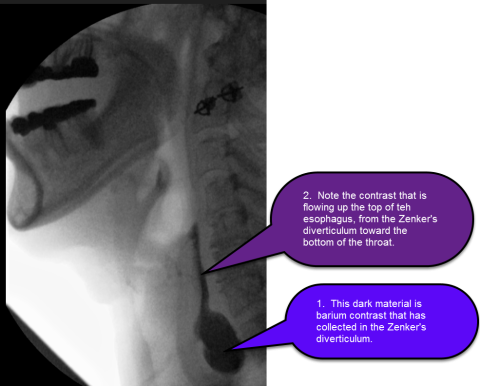

Zenker's diverticulum is diagnosed during upper endoscopy (EGD) or esophagram (aka barium swallow), or a modified barium swallow study (aka videofluoroscopic swallow study) (see figure). These tests complementary during investigation of swallowing problems.